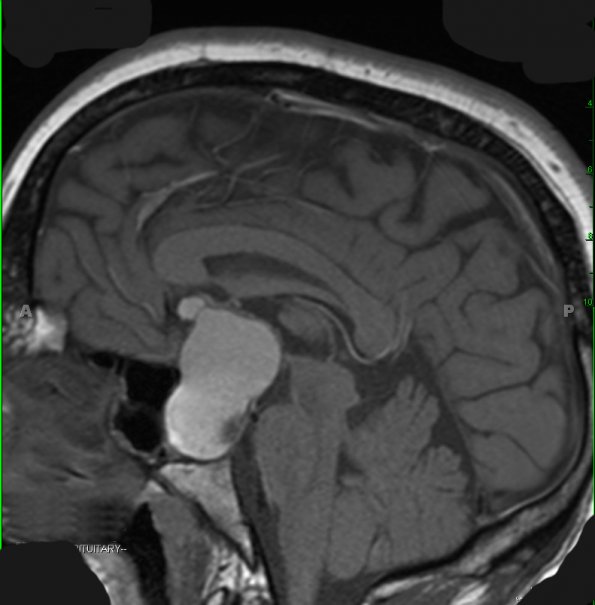

Case 8 History ---- The patient is a 31-year-old man presenting with aches, fatigue, diminished vision, decreased energy, and some blurring of his vision. Work up labs and testing showed he has hypotestosteronism and bitemporal hemianopsia. Head CT scan and brain MRI show a large partially cystic sellar/suprasellar mass with peripheral post-contrast enhancement. Operative procedure: Transsphenoidal excision. ---- Brain MRI shows a large T1-weighted hyperintense partially cystic sellar/suprasellar mass with peripheral post-contrast enhancement.